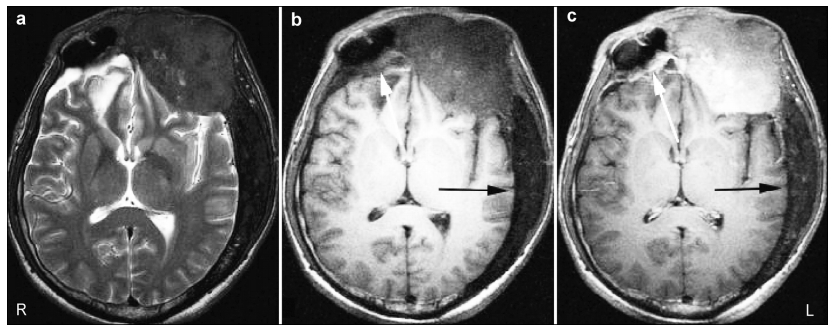

CSF rhinorrhea stopped after the surgery. Twelve days after the fistula repair surgery, enhanced magnetic resonance imaging (MRI) was performed to evaluate the effect of the operation and to obtain more infor-mation about the FD lesions (Figure 4). A nineteen-month follow up was made. The patient recovered well and CSF leakage did not recur. However, the sight of the patient’s left eye had decreased during the last month. A repeat CT scan was performed, which showed that the compression of the left optic nerve seemed to be more severe than nineteen months ago (Figure 5). MAS was suspected. Decompression sur-gery of the left optic nerve canal and laboratory tests of serum hormones were proposed, but the patient refused them. No other new neurological deficits appeared during the follow-up period.

| Figure 4 Axial MRI demonstrating abnormal thickening of the bones in a patient with FD. (a) T2-weighted images show the involved skull bones are hypointense. (b, c) T1-weighted images show the involved skull bones are hypointense (b) with varying enhancement (c). Left frontal bone and the wall of the right frontal sinus showed evident enhancement (white arrows) while the left posterior skull bones did not (black arrows). |

| Figure 5 (a, b) CT showing the left optic canal before and nineteen months after surgery (arrows). The compression of the left optic nerve was more severe at nineteen months after surgery (right) than before surgery (left). |

FD represents about 2.5% of all primary bone masses and 7% of benign bone masses[6]. Three main histological types have been identified in FD: the “Chinese letters” model, the “pagetoid” model, and the “hypercellular” model. Each of these is differentiated on the basis of the architecture and cellularity of the osseous tissue[7]. CT is recommended to define the anatomy of individual lesions and to establish the extent of disease in CFD[5, 8]. The natural radiographic progression may vary from a “ground-glass” or homogenous appearance to a mixed radio-dense/ radio-lucent lesion as the patient ages. The radiographic density of the lesions depends on the proportion of fibrous and osseous elements[7]. MRI is a complemen-tary method to CT, and it is used to examine cranial nerve involvement and obtain more information about the lesion[9]. The signal intensities of FD are usually low on T1-weighted images, but often variable on T2-weighted images, ranging from low-to-high signals[10]. Enhanced MRI often indicates the involved bones contain numerous small vessels and fibrous elements[3].

The first was pathological changes in the skull bone. FD is characterized by the excessive formation of fibrous tissue in the bone marrow and the destruction of normal bone in conjunction with abnormal bone formation and increased osteoclast activity[11]. Normal bone tissue is replaced by the gradual abnormal pro-liferation of fibrous tissue[9]. These pathological changes weaken the structural integrity of the involved bones[12]. Under slight stress, these bones tend to deform and might even fracture[13]. As the limbs, especially both lower limbs, usually bear most of the mechanical stress during daily life, pathologic fractures often occur in these bones with FD. Without significant stress, skull bones with FD rarely fracture. However, when a CFD patient suffers from head trauma, these skull bones might fracture more easily than normal bones. In our patient, CFD was involved in multiple skull bones, including the right frontal bone. A CT scan indicated a low density of the involved right frontal bone (Figure 1), and enhanced MRI showed evident enhan-cement of the right frontal sinus wall (Figure 4). This suggested that the bone in right frontal sinus wall contained numerous small vessels and fibrous elements[3], which would decrease the strength of the bone. These pathological changes increased the risk of fractures after head trauma. As the enhanced MRI was performed after surgery, the enhancement of right frontal sinus posterior wall might also be caused by a healing reaction. However, because the anterior wall of right frontal sinus and surrounding involved bones were also enhanced, it was reasonable to presume that the enhanced effect was mainly caused by pathological changes due to FD.

The surgical treatment of CFD aims to correct the facial deformity in most cases and restore the obliterated foramina, when it the cause of problems. However, this can result in recurrence in 15%-20% of all cases, especially during the growth period[7, 23]. The most devastating consequence of CFD is the loss of vision due to optic nerve compression (ONC). There has been significant controversy regarding the manage-ment of FD of the sphenoid bones that encase the optic nerve, particularly in patients whose vision is normal. A meta-analysis[24] showed that most patients with CFD remain asymptomatic during long-term follow-up, and therefore expectant management is recommended in asymptomatic patients even in the presence of radiological evidence of ONC. Lee et al.[5]recommended that FD in the skull base around vital structures, including the optic nerve, should be managed according to the clinical examination and regular diagnostic imaging and observation is appro-priate in asymptomatic patients. When visual change or vision loss occurs due to ONC, decompression surgery can be performed. In this case, the patient’s age was over 30 years and a CT scan of the involved skull bones showed a mixed appearance (Figure 1). This indicated that the involved bones had entered a stable period. However, nineteen months later, sight in the patient’s left eye had decreased. A CT scan showed that compression of the left optic nerve was more severe than at nineteen months previously (Figure 5). MAS was suspected. Unfortunately, the patient refused to undergo the proposed decompression surgery and laboratory tests of serum hormones.